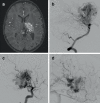

Background: Adenosine induced cardiac standstill has been used intraoperatively for both aneurysm and arteriovenous malformation (AVM) surgery and embolization. We sought to report the results of adenosine induced cardiac standstill as an adjunct to endovascular embolization of brain AVMs.

Results: We identified 47 patients (22 female, 47%) with average age 42 ± 17 years (range 6-77 years) who had undergone AVM embolization procedures using adjunctive circulatory standstill with adenosine. In total there were 4 Spetzler Martin grade 1 (9%), 9 grade 2 (18%), 15 grade 3 (32%), 8 grade 4 (18%), and 11 grade 5 (23%) lesions. Of the AVMs six were ruptured or had previously ruptured. The average number of embolization procedures per patient was 5.7 ± 7.6 (range 1-37) with an average of 2.6 ± 2.2 (range 1-14) embolization procedures using adenosine. Overall morbidity was 17% (n = 8/47) and mortality 2.1% (n = 1/47), with permanent morbidity seen in 10.6% (n = 5/47) postembolization. Angiographic follow-up was available for 32 patients with no residual shunt seen in 26 (81%) and residual shunts seen in 6 patients (19%). The angiographic follow-up is still pending in 14 patients. At last follow-up 93.5% of patients were mRS ≤2 (n = 43/46).

Conclusion: Adenosine induced cardiac standstill represents a viable treatment strategy in high flow AVMs or AV shunts that carries a low risk of mortality and permanent neurological deficits.